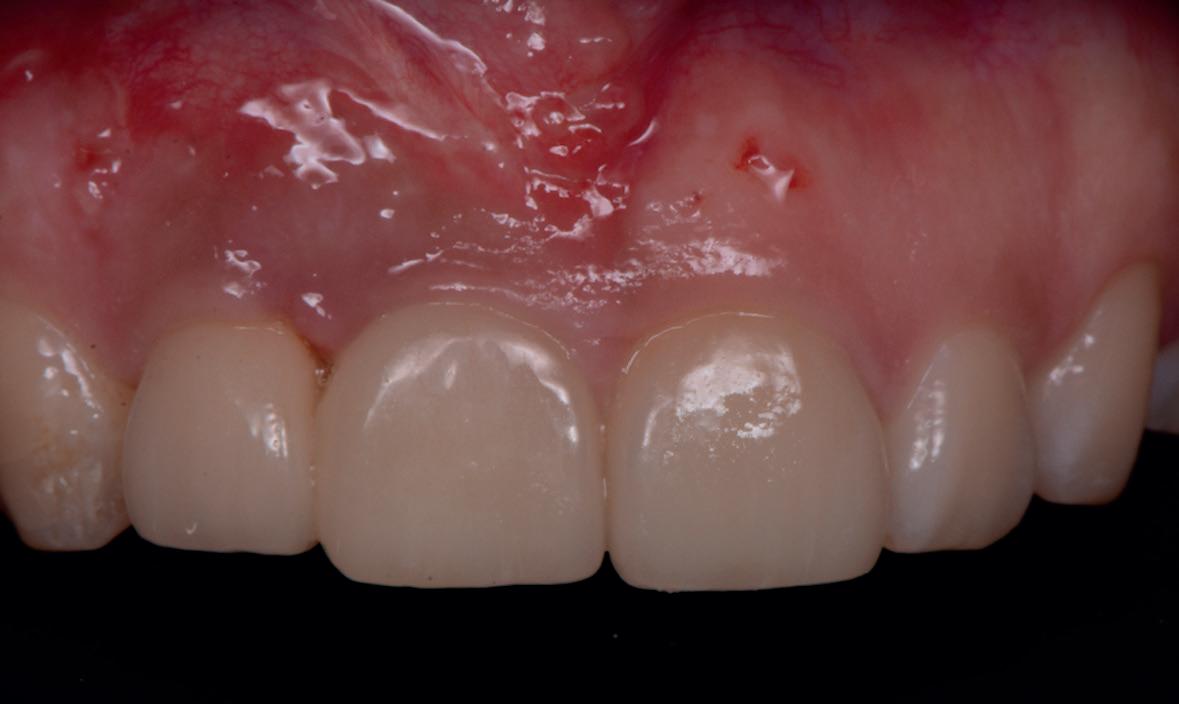

SITE AUGMENTATION Reconstituirea țesutului moale periimplantar și papilar în zona estetică

RECONSTITUIREA țesuturilor moi periimplantare. Scopul acestui raport de caz este de a demonstra procedurile chirurgicale utilizate pentru corectarea unui defect al țesuturilor moi periimplantare folosind țesutul moale interdentar în combinație cu tuberozitatea ca locație donatoare de țesut conjunctiv, utilizând o abordare prin tunelizare într-o zonă estetică.